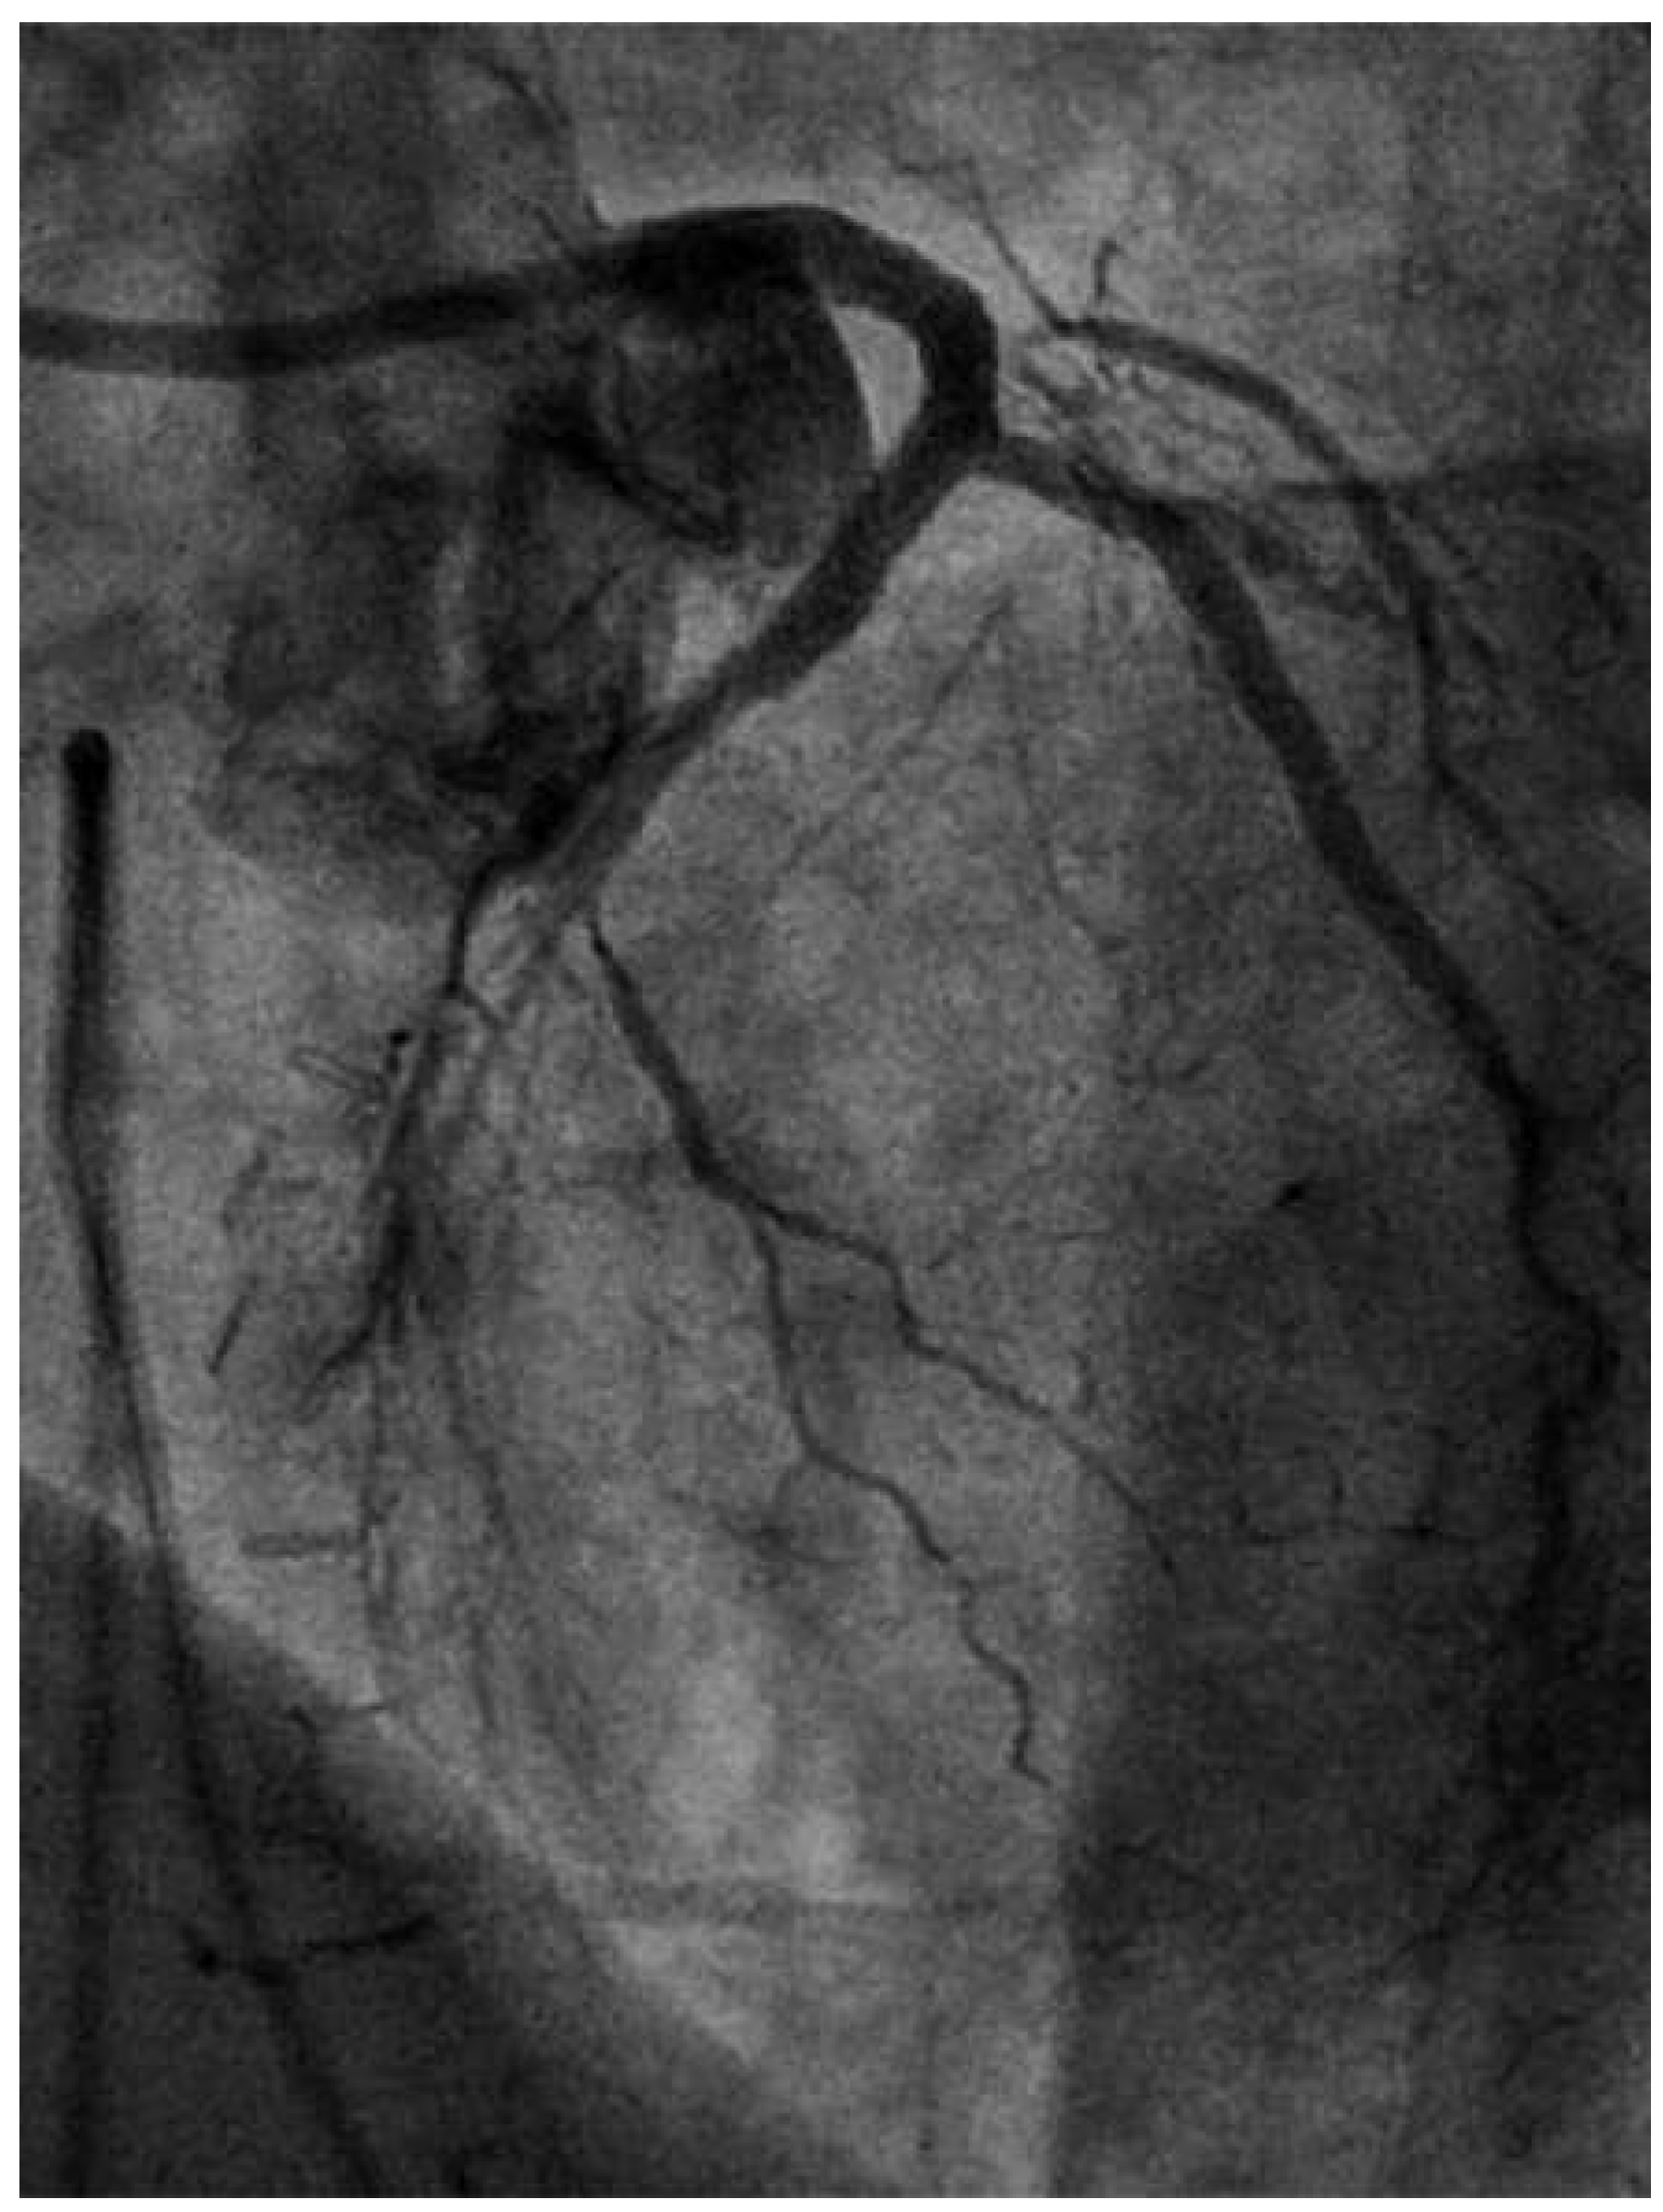

Following RA, both LAD and diagonal were wired with ease using separate Runthrough (Terumo, Japan) wires. Predilatation of both bifurcation limbs was undertaken using 1.5 × 15 mm Trek (Abbott) and 2.0 × 10 mm Sapphire (Orbus-Neich, Hong Kong, China) semicompliant balloons, which both expanded well at nominal pressure. Intending to perform an elective T-stent strategy, a 2.25 × 28 mm Promus Premier DES was deployed at 18 Atm in the diagonal branch, landing proximally at the ostium of this vessel (Figure 3). After removal of the diagonal wire, a 3 × 38 Promus Premier stent (Boston Scientific) was sited from the origin of the LMS across the first diagonal and deployed at 18 Atm (Figure 4). The diagonal branch was then rewired with the runthrough wire. A kissing inflation was performed at 12 Atm using a 3.5 × 12 Quantum (Boston Scientific) and 2.5 × 12 Sapphire noncompliant (NC) balloons in LAD and diagonal, respectively (Figure 5A). The proximal LAD and LMS were then optimised using the 3.5 Quantum NC (LAD) and a Hiryu (Terumo) 4 × 10 NC (LMS) balloons at 22 and 18 Atm, respectively (Figure 5B). The final angiographic result was excellent (Figure 6). Intravascular ultrasound of the LMS was not undertaken as angiographically the LMS stent already appeared completely expanded and oversized. We opted not to intervene in the ostial left Cx in order to best preserve the geometry of the LMS stent.

Figure 4. LAO 30°, cranial 30° view. A Promus Premier 3.0 × 38 stent has been deployed from ostium of LMS across the diagonal.